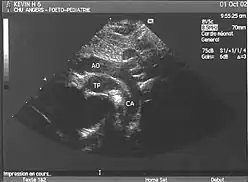

- L'échocardiographie qui est de plus en plus l'examen pratiqué en première intention. Cet examen permet d'affirmer le diagnostic en montrant les anomalies anatomiques, d'apprécier le caractère plus ou moins fonctionnel des shunts cardiaques fœtaux, de rechercher d'autres anomalies associées et dans une certaine mesure d'apprécier le retentissement de la malformation.

- Les coupes échographiques les plus utiles à cette fin sont :

- La coupe parasternale gauche grand axe : elle montre que le vaisseau issu du ventricule gauche (le plus postérieur) se dirige anormalement vers l'arrière et se bifurque précocement. C'est donc le tronc pulmonaire et non l'aorte comme normalement.

- Les coupes sous costales qui montrent bien le trajet parallèle des gros vaisseaux et leur inversion. Cet examen permettra d'éliminer en particulier un retour veineux pulmonaire anormal total bloqué qui aurait pu rendre compte de l’hypervascularisation pulmonaire sur la radiographie des poumons.